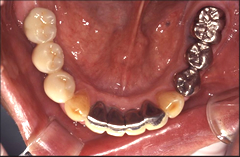

インプラントを埋入する部位の歯肉を開き、顎の骨にインプラントを埋入します。インプラントが骨にしっかり結合するまで約3ヶ月程度待ちます。 この間、必要に応じて仮歯を入れることもできますので、日常生活に差し支えありません。